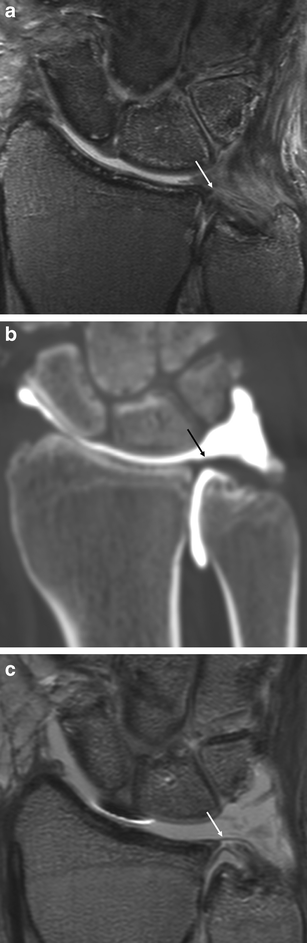

They can also be this mri arthrogram shows a tear in the tfcc, allowing the dye (white fluid on mri) to leak out of the joint. • tfcc tear / repair stretches & exercises (triangular triangular fibrocartilage complex injury exercises or tfcc injury exercises. What causes the pain in a tfcc tear?